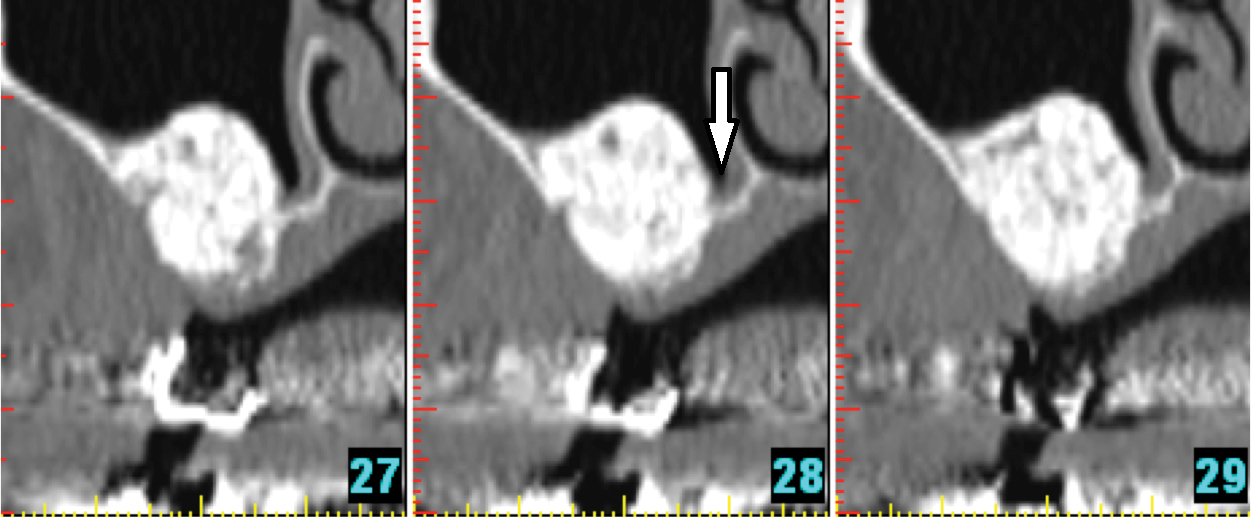

Fig 18. Maxillary sinus: three consecutive cross-sectional views. Pseudocyst in the floor of the sinus (arrow).

Figure 18